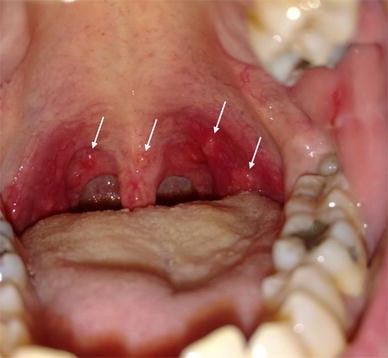

Check if its hand foot and mouth disease. This article presents a brief summary and review of the etiology clinical features diagnosis prognosis and. HFMD blisters may form in the mouth and on the tongue hands feet or.

Hand-foot-and-mouth disease HFMD is a febrile disorder usually caused by coxsackievirus A16 enterovirus 71 or other enteroviruses. 2262020 Hand foot and mouth disease is a common infection that causes mouth ulcers and spots on the hands and feet. Children with HFMD usually get a fever first then red spots with blisters in the middle.